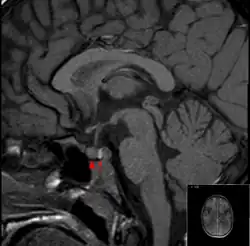

Se recomienda realizar una resonancia magnética (RM) de la hipófisis si se sospecha el diagnóstico; tiene una sensibilidad de más del 90% para detectar la apoplejía hipofisaria; puede demostrar infarto (daño tisular debido a una disminución del riego sanguíneo) o hemorragia.[1] Se pueden utilizar diferentes secuencias de RM para establecer cuándo se produjo la apoplejía y la forma predominante del daño (hemorragia o infarto).[2] Si la RM no es adecuada (por ejemplo, debido a claustrofobia o a la presencia de implantes metálicos), una tomografía computarizada (TC) puede demostrar anomalías en la hipófisis, aunque es menos fiable.[1] Muchos tumores hipofisarios (25%) presentan zonas de infarto hemorrágico en las RM, pero no se considera que exista apoplejía a menos que vaya acompañada de síntomas.[1][4]